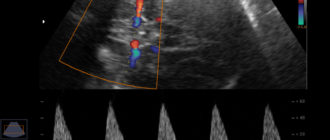

Нарушение маточно-плацентарного кровотока при беременности Беременные женщины и их родные обычно ожидают от УЗИ-обследования

Что такое МППК при беременности. Степени нарушения МППК при беременности На УЗИ, как на